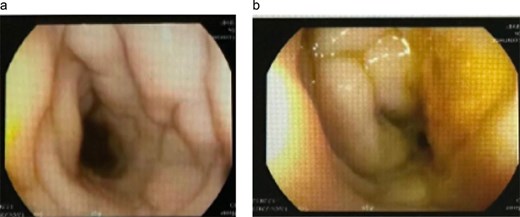

Colonoscopic appearance of the cecal lesion (a, b). Endoscopic views showing a large fungating, circumferential cecal mass with ulcerated, erythematous mucosa, and adherent yellowish exudate causing near-luminal occlusion; biopsies confirmed GIB due to Basidiobolus ranarum.

Image-guided biopsy from the omentum showed non-necrotizing granulomatous inflammation with broad, aseptate fungal hyphae consistent with basidiobolomycosis. Colonoscopy demonstrated a markedly narrowed, inflamed rectosigmoid segment (Fig. 4).

Colonoscopic finding. (a) Colonoscopic views of the rectosigmoid colon demonstrate marked concentric narrowing with pale, edematous mucosal folds and loss of regular vascular pattern, resulting in near-luminal occlusion. (b) These appearances were initially suggestive of severe inflammatory or infiltrative disease and were subsequently proven to represent GIB.